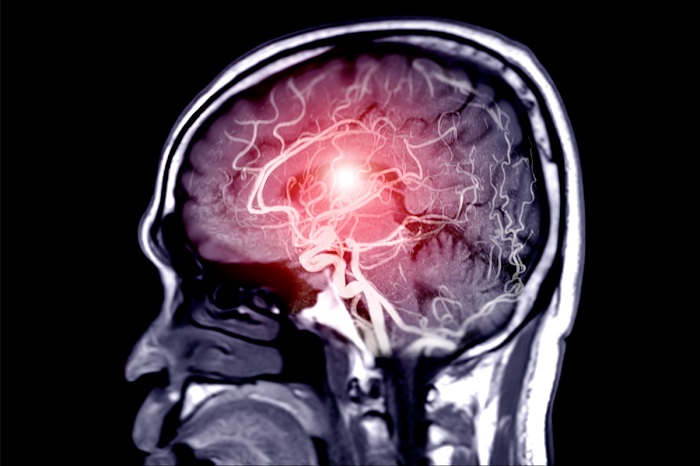

Што е мозочен удар?

Според Кливленд клиниката, мозочен удар е итна медицинска состојба која настанува кога мозокот не добива доволно крв. Затнат крвен сад или крварење во мозокот може да предизвика мозочен удар.

Мозочниот удар трае додека мозокот не добива соодветна количина крв. Мозочните клетки умираат ако предолго останат без кислород од свежа крв. Ако премногу клетки во одреден дел на мозокот умрат, оштетувањето станува трајно, што може да предизвика долготрајни инвалидитети и други промени.

Обновувањето на нормалниот проток на крв може да спречи трајно оштетување или да ја намали неговата сериозност. Затоа, времето е клучно во лекувањето на мозочниот удар. Симптомите и последиците можат да траат една година или подолго.